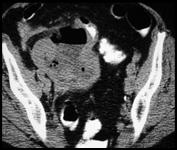

Perforated Appendicitis with right pyosalpinx and pyometra